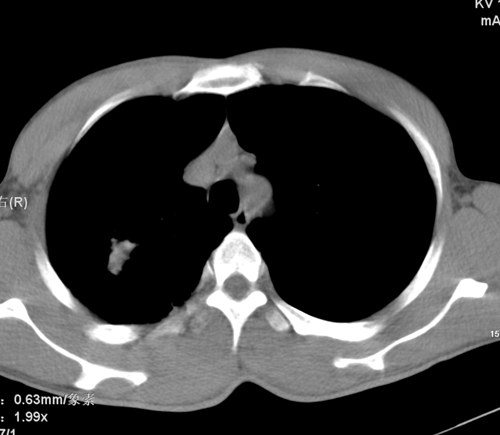

标题: CT24548:男 31 咳嗽 咯血一天 行CT检查 [打印本页]

标题: CT24548:男 31 咳嗽 咯血一天 行CT检查

ct考虑结核 但化验结果示白细胞总数 淋巴均正常,血沉7mm/h不快,请看看结核 支扩还是其他

右肺上叶尖端,后段下叶背段结核伴空洞形成

右肺继发性肺结核伴空洞形成!

右肺继发性肺结核伴右肺下叶背段空洞形成。